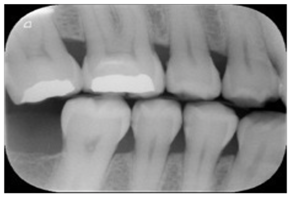

| Bitewing X-rays | [37,49,54,77,84,85,86] | Caries detection (posterior initial proximal caries) | ![]() | Accuracy |